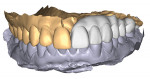

A 32-year-old healthy man, referred by his general dentist, presented with mild numbing sensation symptoms on the left aspect of his maxilla. Four months before the referral, when the patient had no symptoms, a panoramic radiograph revealed the splaying of teeth. Possibly because of the superimposition of radiopaque structures, this went unnoticed. Upon the author's clinical examination, a CBCT revealed a well-defined, multilocular radiolucent lesion present between teeth Nos. 13 and 14. The general behavior of the lesion was rather aggressive. Biopsy results confirmed ameloblastoma, a common benign tumor of the jaws that requires marginal resection due to its high recurrence rate. A treatment plan with the surgical and restorative team was presented to the patient. The treatment would begin with a hemimaxillectomy with secured margins and mucocutaneous fibula graft with implant placement at the time of resection. After 6 months of healing, the second-stage surgery would follow with the insertion of a 3D-printed long-term temporary restoration. Several months later, after occlusion changes and complete healing, the final prosthesis would be inserted. The case was completed in 12 months using a digital workflow plan (DEXIS, dexis.com) that involved the use of intraoral scanning, virtual surgical planning (VSP) software, advanced imaging, exocad software, 3D printing, and more.

· In an extreme case like this, which involves the synergy of the medical and dental team, the digital workflow is crucial to a successful outcome for the patient and the entire team.